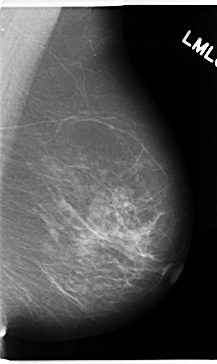

ics_version 1.0 filename C-0172-1 DATE_OF_STUDY 8 5 1996 PATIENT_AGE 70 FILM FILM_TYPE REGULAR DENSITY 2 DATE_DIGITIZED 12 3 1998 DIGITIZER LUMISYS LASER SEQUENCE LEFT_CC LINES 4760 PIXELS_PER_LINE 2616 BITS_PER_PIXEL 12 RESOLUTION 50 NON_OVERLAY LEFT_MLO LINES 4720 PIXELS_PER_LINE 2816 BITS_PER_PIXEL 12 RESOLUTION 50 NON_OVERLAY RIGHT_CC LINES 4696 PIXELS_PER_LINE 2680 BITS_PER_PIXEL 12 RESOLUTION 50 OVERLAY RIGHT_MLO LINES 4640 PIXELS_PER_LINE 2976 BITS_PER_PIXEL 12 RESOLUTION 50 OVERLAY |